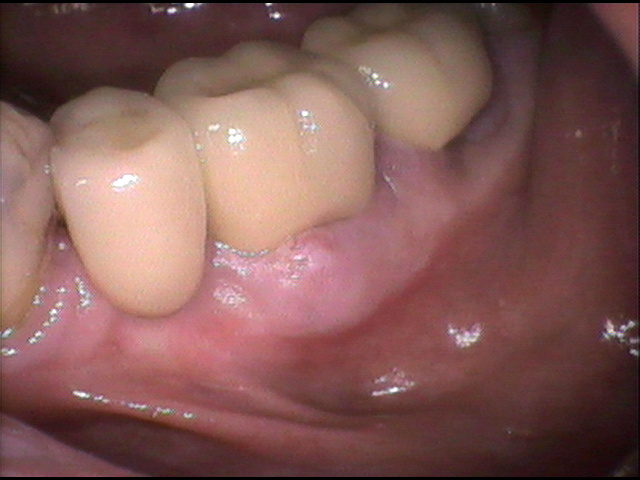

インプラント治療前 61_1

主 訴

下顎奥歯が痛くて噛めない。

年 齢

68歳